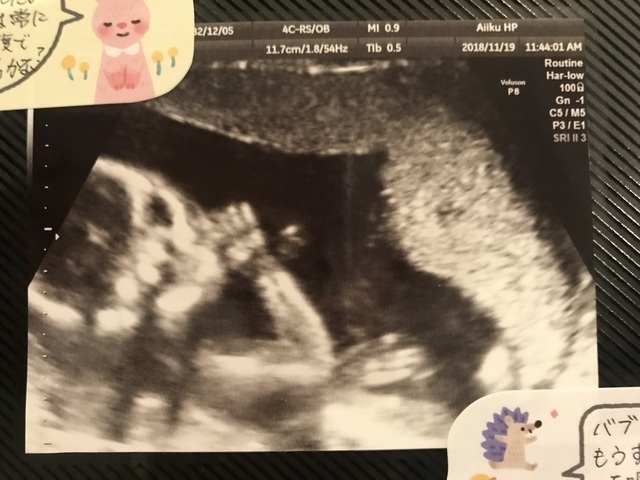

17週4日(17w4d・性別不明)|けのす さん(30歳)

エコー写真撮影時のエピソード:

毎回ちゃんと成長しているのか、ドキドキしながら妊婦健診へ行きます。もしかしたら性別がわかるかもしれないという週数でしたが、残念ながらわからず、でもかわいい小さな足の裏のエコーを先生が上手く撮ってくれて、ほっこりしました。なんども見直してしまいます。